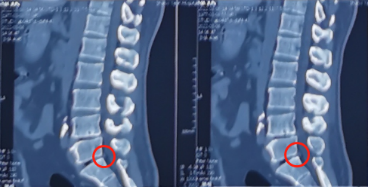

神经脊柱科熊东主任接诊吕先生后,尽快为他安排了各项检查,发现他的腿痛主要是从右侧臀部一直放射到小腿后侧,并且右侧直腿抬高呈阳性,双下肢皮肤浅感觉也出现了减退。根据吕先生拍的CT片子,可以发现腰5骶1椎间盘突出,并且已经严重压迫神经根,这种情况建议尽快进行手术解压。